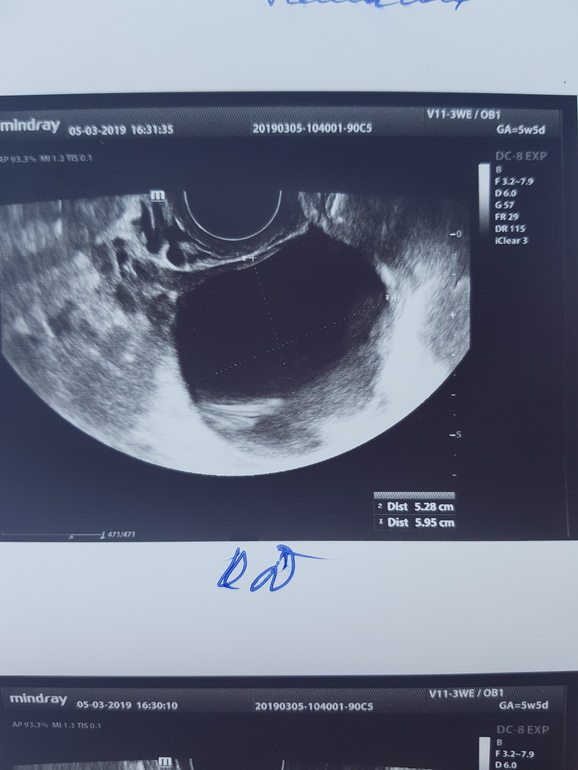

Вчера была на узи, чтобы исключить внематочную. Нашли плодное яйцо 4,3 мм и большую гематому рядом 19,1 на 5,6 мм. И еще кисту желтого тела 5 см.

Киста